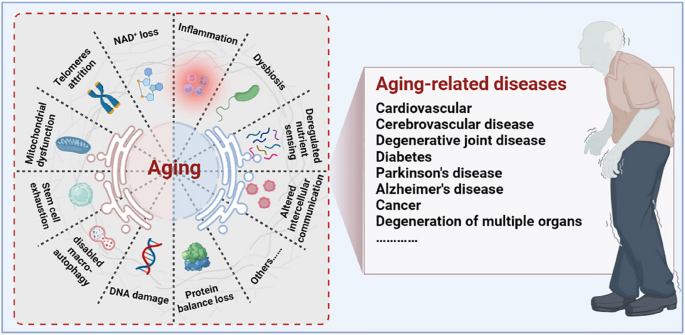

Aging is a progressive degenerative state that can be physiological and pathological [ 7 , 8 , 9 ] (Fig. 1 ). Physiological aging is observed in across many species, and is a degenerative process that occurs after maturation, including telomere attrition [ 10 , 11 ], DNA damage [ 12 , 13 ], mitochondrial dysfunction [ 14 , 15 ], loss of nicotinamide adenine dinucleotide (NAD + ) levels [ 16 , 17 ], impaired macro-autophagy [ 18 , 19 ], stem cell exhaustion, inflammation [ 20 , 21 ], loss of protein balance [ 22 ], deregulated nutrient-sensing [ 23 ], altered intercellular communication [ 24 , 25 , 26 ] and dysbiosis [ 27 , 28 ], thereby leading to systemic functional decline. Importantly, these changes are decentralised and interactive, not independent of each other. Pathological aging includes the senile pathological aging changes, which are caused by various external factors, such as cardiovascular disease [ 29 ], cerebrovascular disease [ 30 ], degenerative joint disease [ 31 , 32 ], diabetes [ 33 ], Parkinson’s disease [ 34 , 35 ], Alzheimer’s disease [ 36 ], cancer [ 37 , 38 , 39 ], and degeneration of multiple organ functions. These aging-induced cellular physiological and pathological changes can reflect the underlying nutrient sensing, intercellular communication, protein stabilisation, epigenetics, and molecular abnormalities in DNA damage repair, leading to genomic instability and damage. Further understanding of the different molecular mechanisms involved in the aging process is of great importance for preventing aging and prolonging the lifespan.

Aging drivers and age-related diseases. Major physiological features of aging include NAD + loss, telomeres attrition, mitochondrial dysfunction, stem cell exhaustion, disabled macro-autophagy, DNA damage, protein balance loss, inflammation, dysbiosis, deregulated nutrient sensing, and altered cellular communication. These physiological characteristics of aging are primitive, antagonistic, and integrated, and their interaction promotes aging. When aging reaches a certain threshold, organ and tissue function continues to deteriorate, which increases the incidence and mortality of aging-related diseases, including cardiovascular, cerebrovascular, degenerative joint disease, diabetes, Parkinson’s disease, Alzheimer’s disease, and cancer